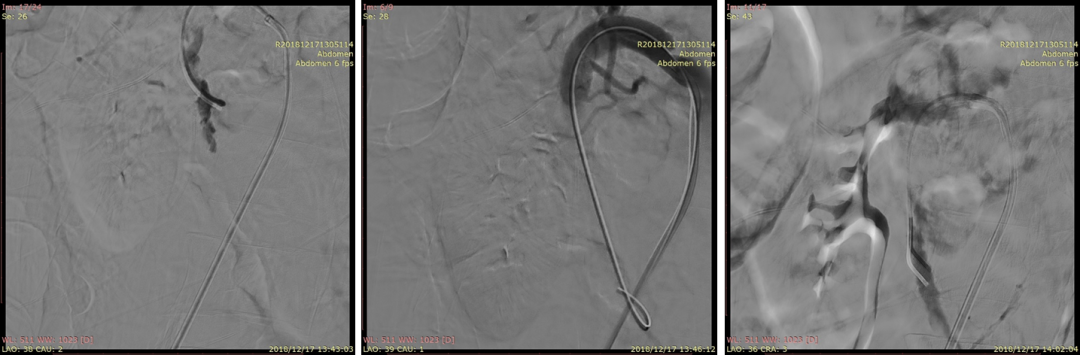

20181217DSA:植入第一枚支架(wallstent7*50mm)

20181217DSA:植入第二枚支架(wallstent9*50mm)

20181217DSA:支架植入后尝试寻找空肠动脉

20181217DSA:支架植入后最终复查造影